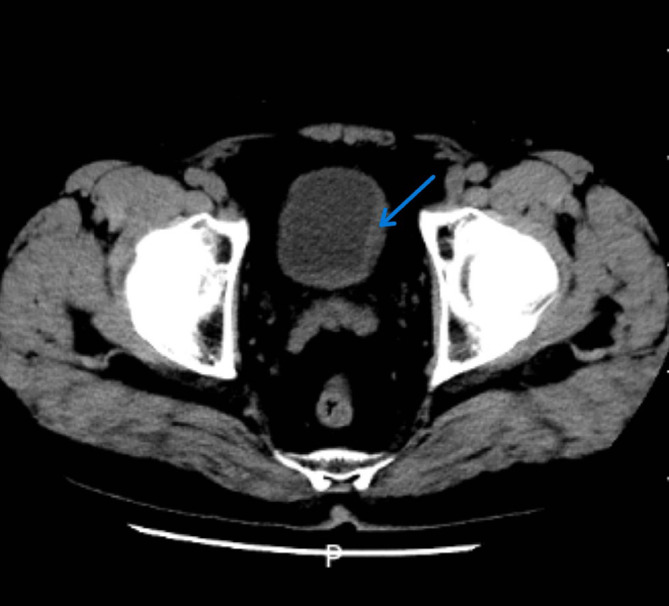

Figure 2.

CT of the bladder: the blue arrow marks the location of the patient’s bladder wall thickening.

On July 11, 2022, he was admitted to our nephrology department for treatment. A routine urine examination showed 434.1/μL white blood cells, 53.7/μL red blood cells and 64.9/μL bacteria (Figure 1). Blood sedimentation 44 mm/h; C-reactive protein 16.82 mg/L; no abnormalities in routine blood (Table 1); renal function: creatinine 124 μmol/L, urea 8.58 mmol/L; no abnormalities in urine culture. Anti-nuclear antibody +1:320; anti-dsDNA antibody 131.1 IU/mL. Urological ultrasound: right kidney stone, left hydronephrosis and left ureteral dilatation. Computed Tomography (CT) of kidneys and bladder: 1. Stones in both kidneys; 2. Thickening of the left posterior wall of the bladder with hydronephrosis of the left kidney and dilated effusion of the left ureter; 3. Cyst in the right kidney (Figure 2). We considered complicated urinary tract infections, interstitial cystitis, and poor anti-infective effect. On day 18 of admission, urethral stricture dilatation, transurethral suburethral cystoscopy, hydrodistension and cystocentesis biopsy were performed. Pathology showed a microscopic examination of transverse muscle and a little fibrous and fatty tissue. On the 24th day of admission, the urine test was repeated: white blood cells 951.3/μL, red blood cells 1258.8/μL and bacterial count 274.7/μL. The patient requested to be discharged after his condition was more stable than before.